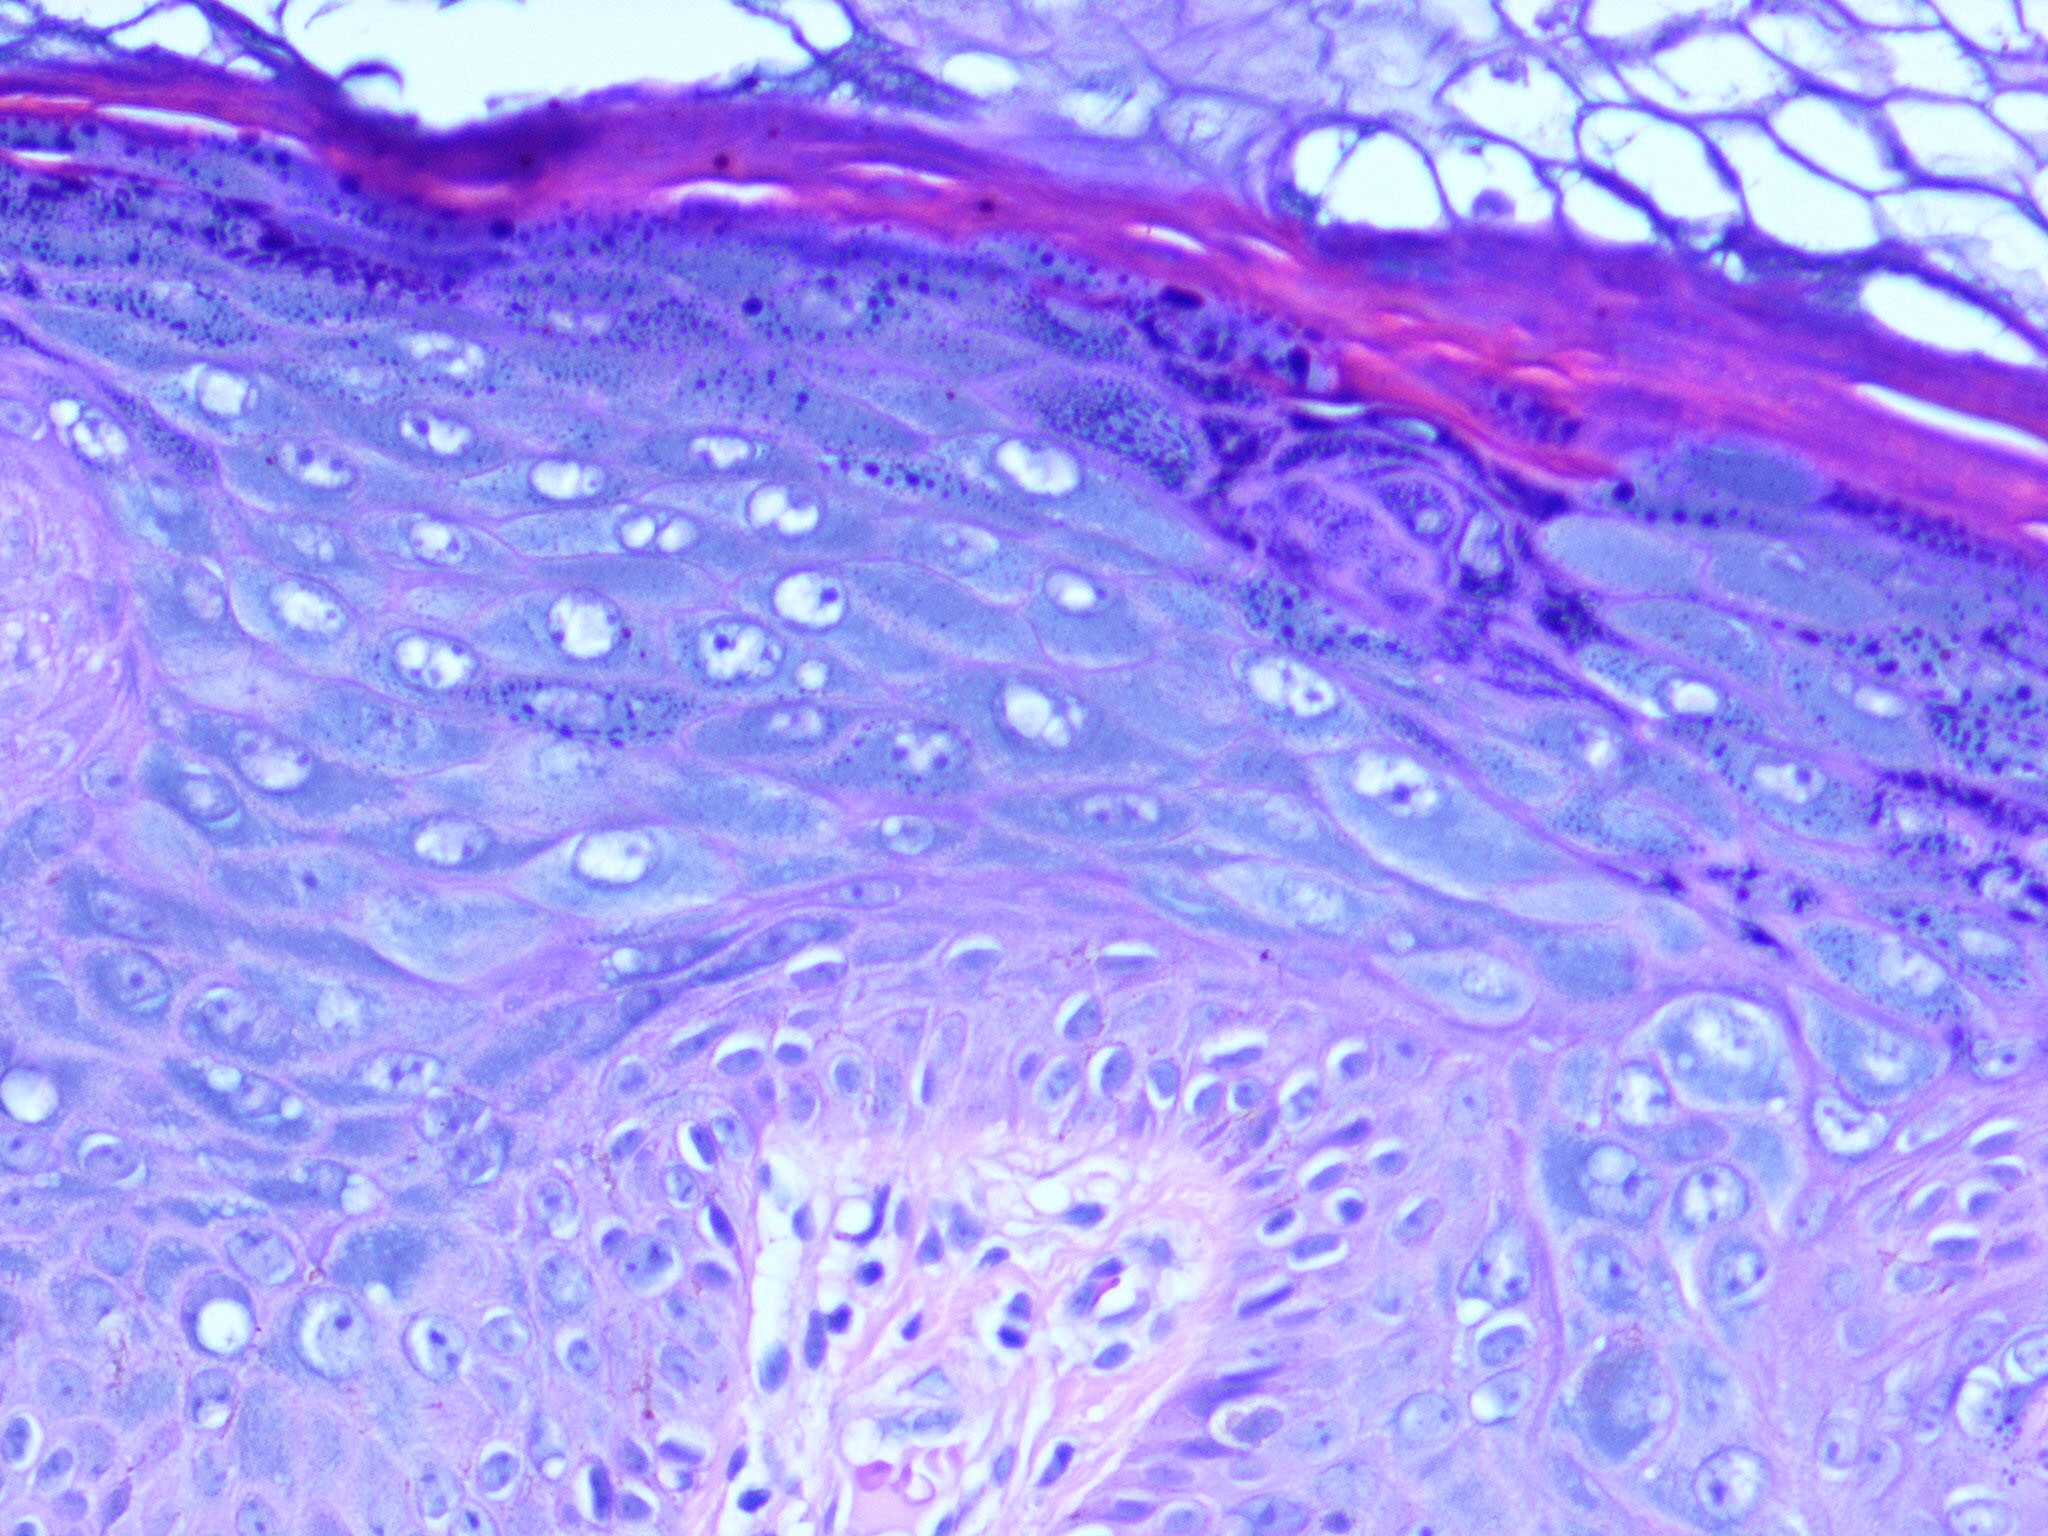

Epidermodysplasia Verruciformis =عسر تصنع البشرة الثؤلولي